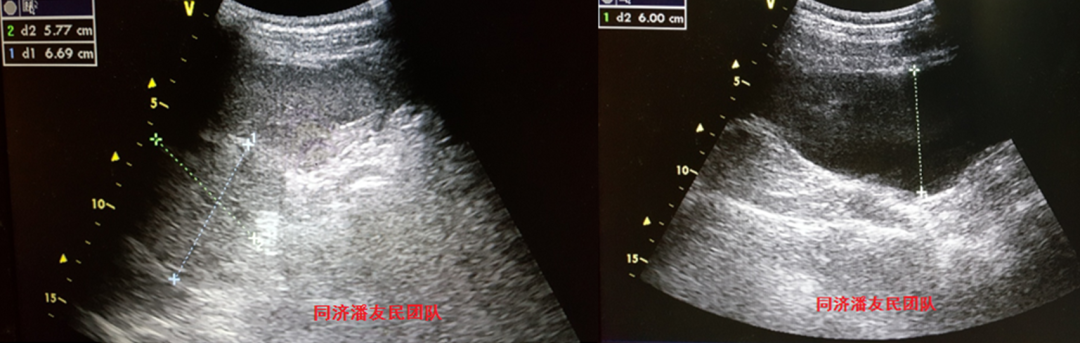

腹部彩超也证实脾破裂,腹腔积血(图4)。

图4:腹部彩超显示脾脏区域5*6 cm混合型暗区,腹腔6 cm液性暗区。